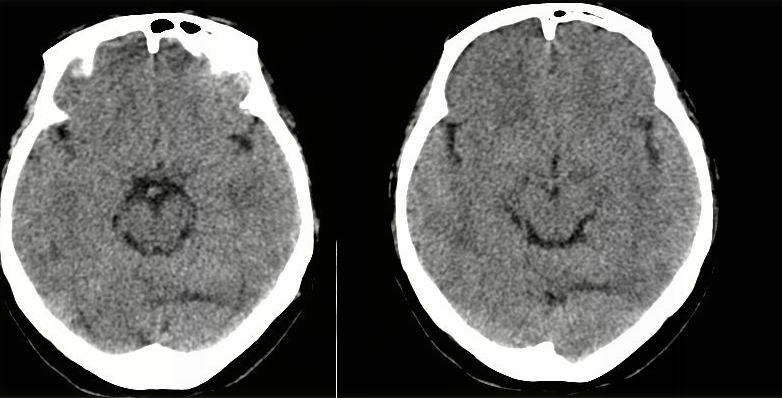

病人资料:女,57岁,反复头痛6年余,无恶心、呕吐等症状,体查:bp180/100mmhg。

胼胝体发育不良并脂肪瘤形成,脂肪瘤形成是因,胼胝体发育不良是果。如果正规些应该是中线脂肪瘤并胼胝体发育不良!

典型中线脂肪瘤

胼胝体发育不良

中线脂肪瘤并胼胝体发育不良。